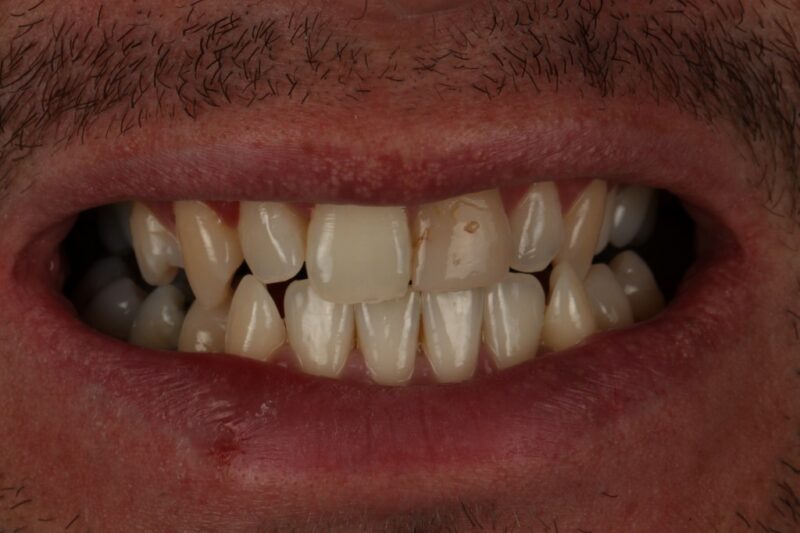

An extremely difficult case where 4 composite veneers were used to change the look of the teeth underneath. The teeth were very thin and the…

Read moreComposite Bonding Gallery Case 31